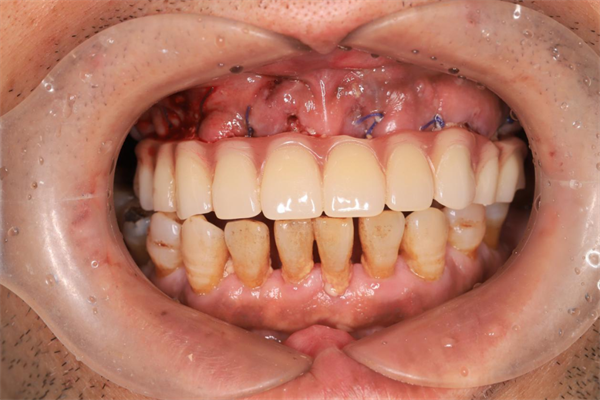

過渡義齒即刻戴牙(告別拔牙后缺牙期)